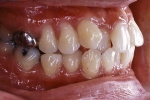

治療後5年経過時